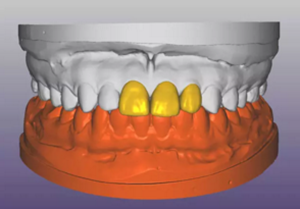

(1)術(shù)前準(zhǔn)備。拍攝臨床照片、拍攝輕開口位CBCT(NewTom)、取聚醚印模灌制超硬石膏模型。 構(gòu)建數(shù)字化模型并設(shè)計修復(fù)體:將超硬石膏模型在口外掃描(Identica? Hybrid),獲取軟硬組織表面形態(tài),構(gòu)建數(shù)字化模型,確認咬合情況。根據(jù) 天然牙殘根頸部形態(tài)設(shè)計修復(fù)體頸部形態(tài),使修復(fù)體頸緣輪廓與原有天然牙 一致;按正常牙弓弧度與覆 、覆蓋關(guān)系,結(jié)合紅白美學(xué)等原則確定修復(fù)體 的三維形態(tài)。最后,導(dǎo)入患者面部照片,確認模擬修復(fù)效果。 設(shè)計種植體位置并制作多級導(dǎo)板:利用Segma設(shè)計軟件,將CBCT數(shù)據(jù) 和模型掃描數(shù)據(jù)進行配準(zhǔn),調(diào)入模擬修復(fù)效果數(shù)據(jù),以修復(fù)為導(dǎo)向設(shè)計種植 方案,設(shè)計種植體螺絲孔開口從修復(fù)體舌窩處穿出,最終實現(xiàn)螺絲固位的一 體化基臺冠修復(fù)。根據(jù)種植體信息設(shè)計多級導(dǎo)板,參考修復(fù)體形態(tài)設(shè)計導(dǎo)板 植入?yún)^(qū)頸緣外形,打印生成種植導(dǎo)板(Segma),并安裝金屬引導(dǎo)環(huán)。 設(shè)計并制作臨時修復(fù)體:如前所述,按照美學(xué)效果和咬合關(guān)系設(shè)計臨 時冠外形,頸部形態(tài)與模型齦緣輪廓一致,保證臨時修復(fù)體在術(shù)后可以封閉 拔牙窩。3顆臨時冠為連冠,齦外展隙適當(dāng)加大,為術(shù)后軟組織生長提供一 定的空間。在臨時冠近兩側(cè)鄰牙的切角處預(yù)留翼板,保證臨時冠戴入時可以 找到準(zhǔn)確的位置。以銑削的方式加工臨時冠(Segma),待種植體植入后 將其在口內(nèi)粘接于臨時基臺上。

圖4 構(gòu)建數(shù)字化模型并設(shè)計修復(fù)體

圖5 設(shè)計種植體位置與多級導(dǎo)板

圖6 設(shè)計臨時修復(fù)體